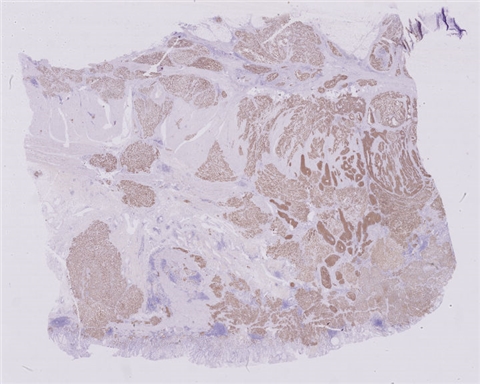

患者详情: 患者4月前开始出现上腹胀痛不适,进食后加重,伴梗咽感,不伴恶心呕吐、腹泻便秘、畏寒发热等不适,因症状持续遂当地医院就诊,行电子胃镜检查示:贲门-胃体CA? 胃镜:贲门、胃底见一大小约2.0*1.5厘米不规则溃疡面,覆污苔,取检质脆易出血,粘液湖清。 CT:贲门胃底区壁不规则增厚并软组织肿块影,边界不清,突向腔外,邻近胃周脂肪毛糙,增强呈明显不均匀、持续性强化,胃周结构层次毛糙,胃周见稍大淋巴结,呈中等欠均匀强化。贲门胃底区增厚并肿块,胃周浸润,请结合胃镜检查。 肿瘤标志物:CEA、CA199、CA125均正常

大体所见: 全胃切除标本:大弯长24cm,小弯长15cm,附网膜14*11.5*5cm,距贲门切缘2cm处于小弯侧见4.5*4.5*2.5cm溃疡性肿物,切面灰白色,实性,质硬,肉眼侵及全层。

医院: 南昌大学第二附属医院